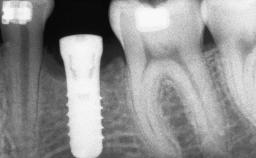

Bone Augmentation Horizontal|Sinus Floor Elevation|Staged|Vertical

Augmentation Materials Autogenous chips|Autogenous block(s)

Bone Volume Deficient vertically or deficient vertically AND horizontally